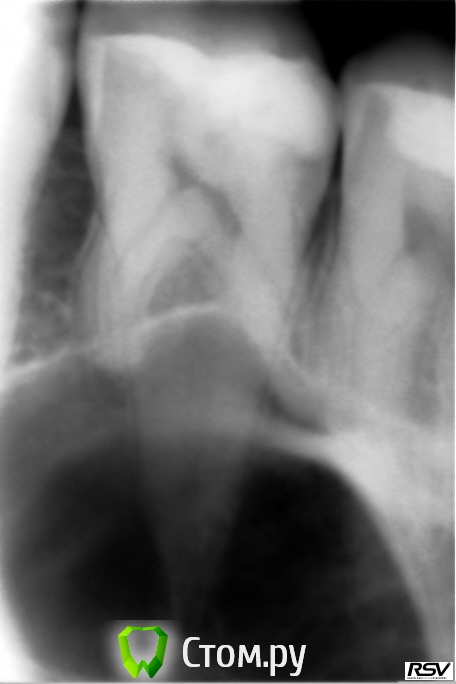

drkr8 Опубликовано 4 июня, 2014 Поделиться Опубликовано 4 июня, 2014 Здравствуйте, хотелось бы услышать оценку данным снимкам, потому что 4 разные клиники говорят разное. Ссылка на комментарий

IvanK Опубликовано 4 июня, 2014 Поделиться Опубликовано 4 июня, 2014 Кистой пугают? Ссылка на комментарий

drkr8 Опубликовано 4 июня, 2014 Автор Поделиться Опубликовано 4 июня, 2014 Кистой пугают? Все верно. Ссылка на комментарий

Гарриевич Опубликовано 5 июня, 2014 Поделиться Опубликовано 5 июня, 2014 Это гайморова пазуха ) 3 Ссылка на комментарий

drkr8 Опубликовано 5 июня, 2014 Автор Поделиться Опубликовано 5 июня, 2014 Хотелось бы услышать комментарий по поводу зуба. Стоматолог клиники сказал, что корни очень далеко идут, пломба очень массивная и давит на него, поэтому зуб нужно удалить. Ссылка на комментарий

faity Опубликовано 5 июня, 2014 Поделиться Опубликовано 5 июня, 2014 удалить всегда успеете, сделайте КТ. сколько полных лет, ещё вопрос? Ссылка на комментарий

faity Опубликовано 6 июня, 2014 Поделиться Опубликовано 6 июня, 2014 делайте КТ и лечите, потом коронку с вкладкой и никаких пломб Ссылка на комментарий